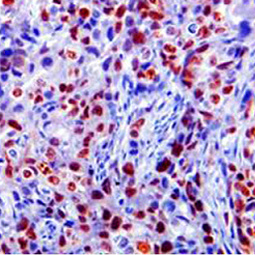

Stresses to cells and organisms originate from a variety of sources, including mechanical injury, pathogens, toxic compounds in the environment, naturally occurring agents that damage cells such as ultraviolet light, nutrient or oxygen deprivation, and many more. These cellular stressors damage macromolecules, cells, and organisms in several ways from altering the normal function of cells and tissues to perturbing the growth and reproduction of the organism. Consequently organisms have evolved many strategies to respond to stresses, such as cell proliferation, apoptosis, autophagy, senescence, inflammation and immunity that ensure efficient recovery and reestablish homeostasis. The inability to manage cellular and organismal stress often leads to disease and underlies the aging process. Our research groups study cell and organismal stress and the response to stress in the context of plant pathogenesis, DNA damage, viral infection, growth factor dysregulation, oxygen deprivation, among others.